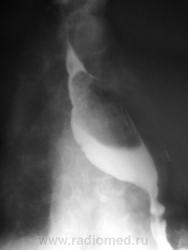

Пациентка, весьма преклонного возраста направлена на исследование желудка. Диагноз - язвенная болезнь желудка. Ну с желудком вроде-бы нормально, но вот с пищеводом возникли заморочки. Все осложнилось еще и тем, что пациентка в вертикальном положении смогла побыть секунд 40.

Ниже снимки, которые смогли провести в положении стоя.